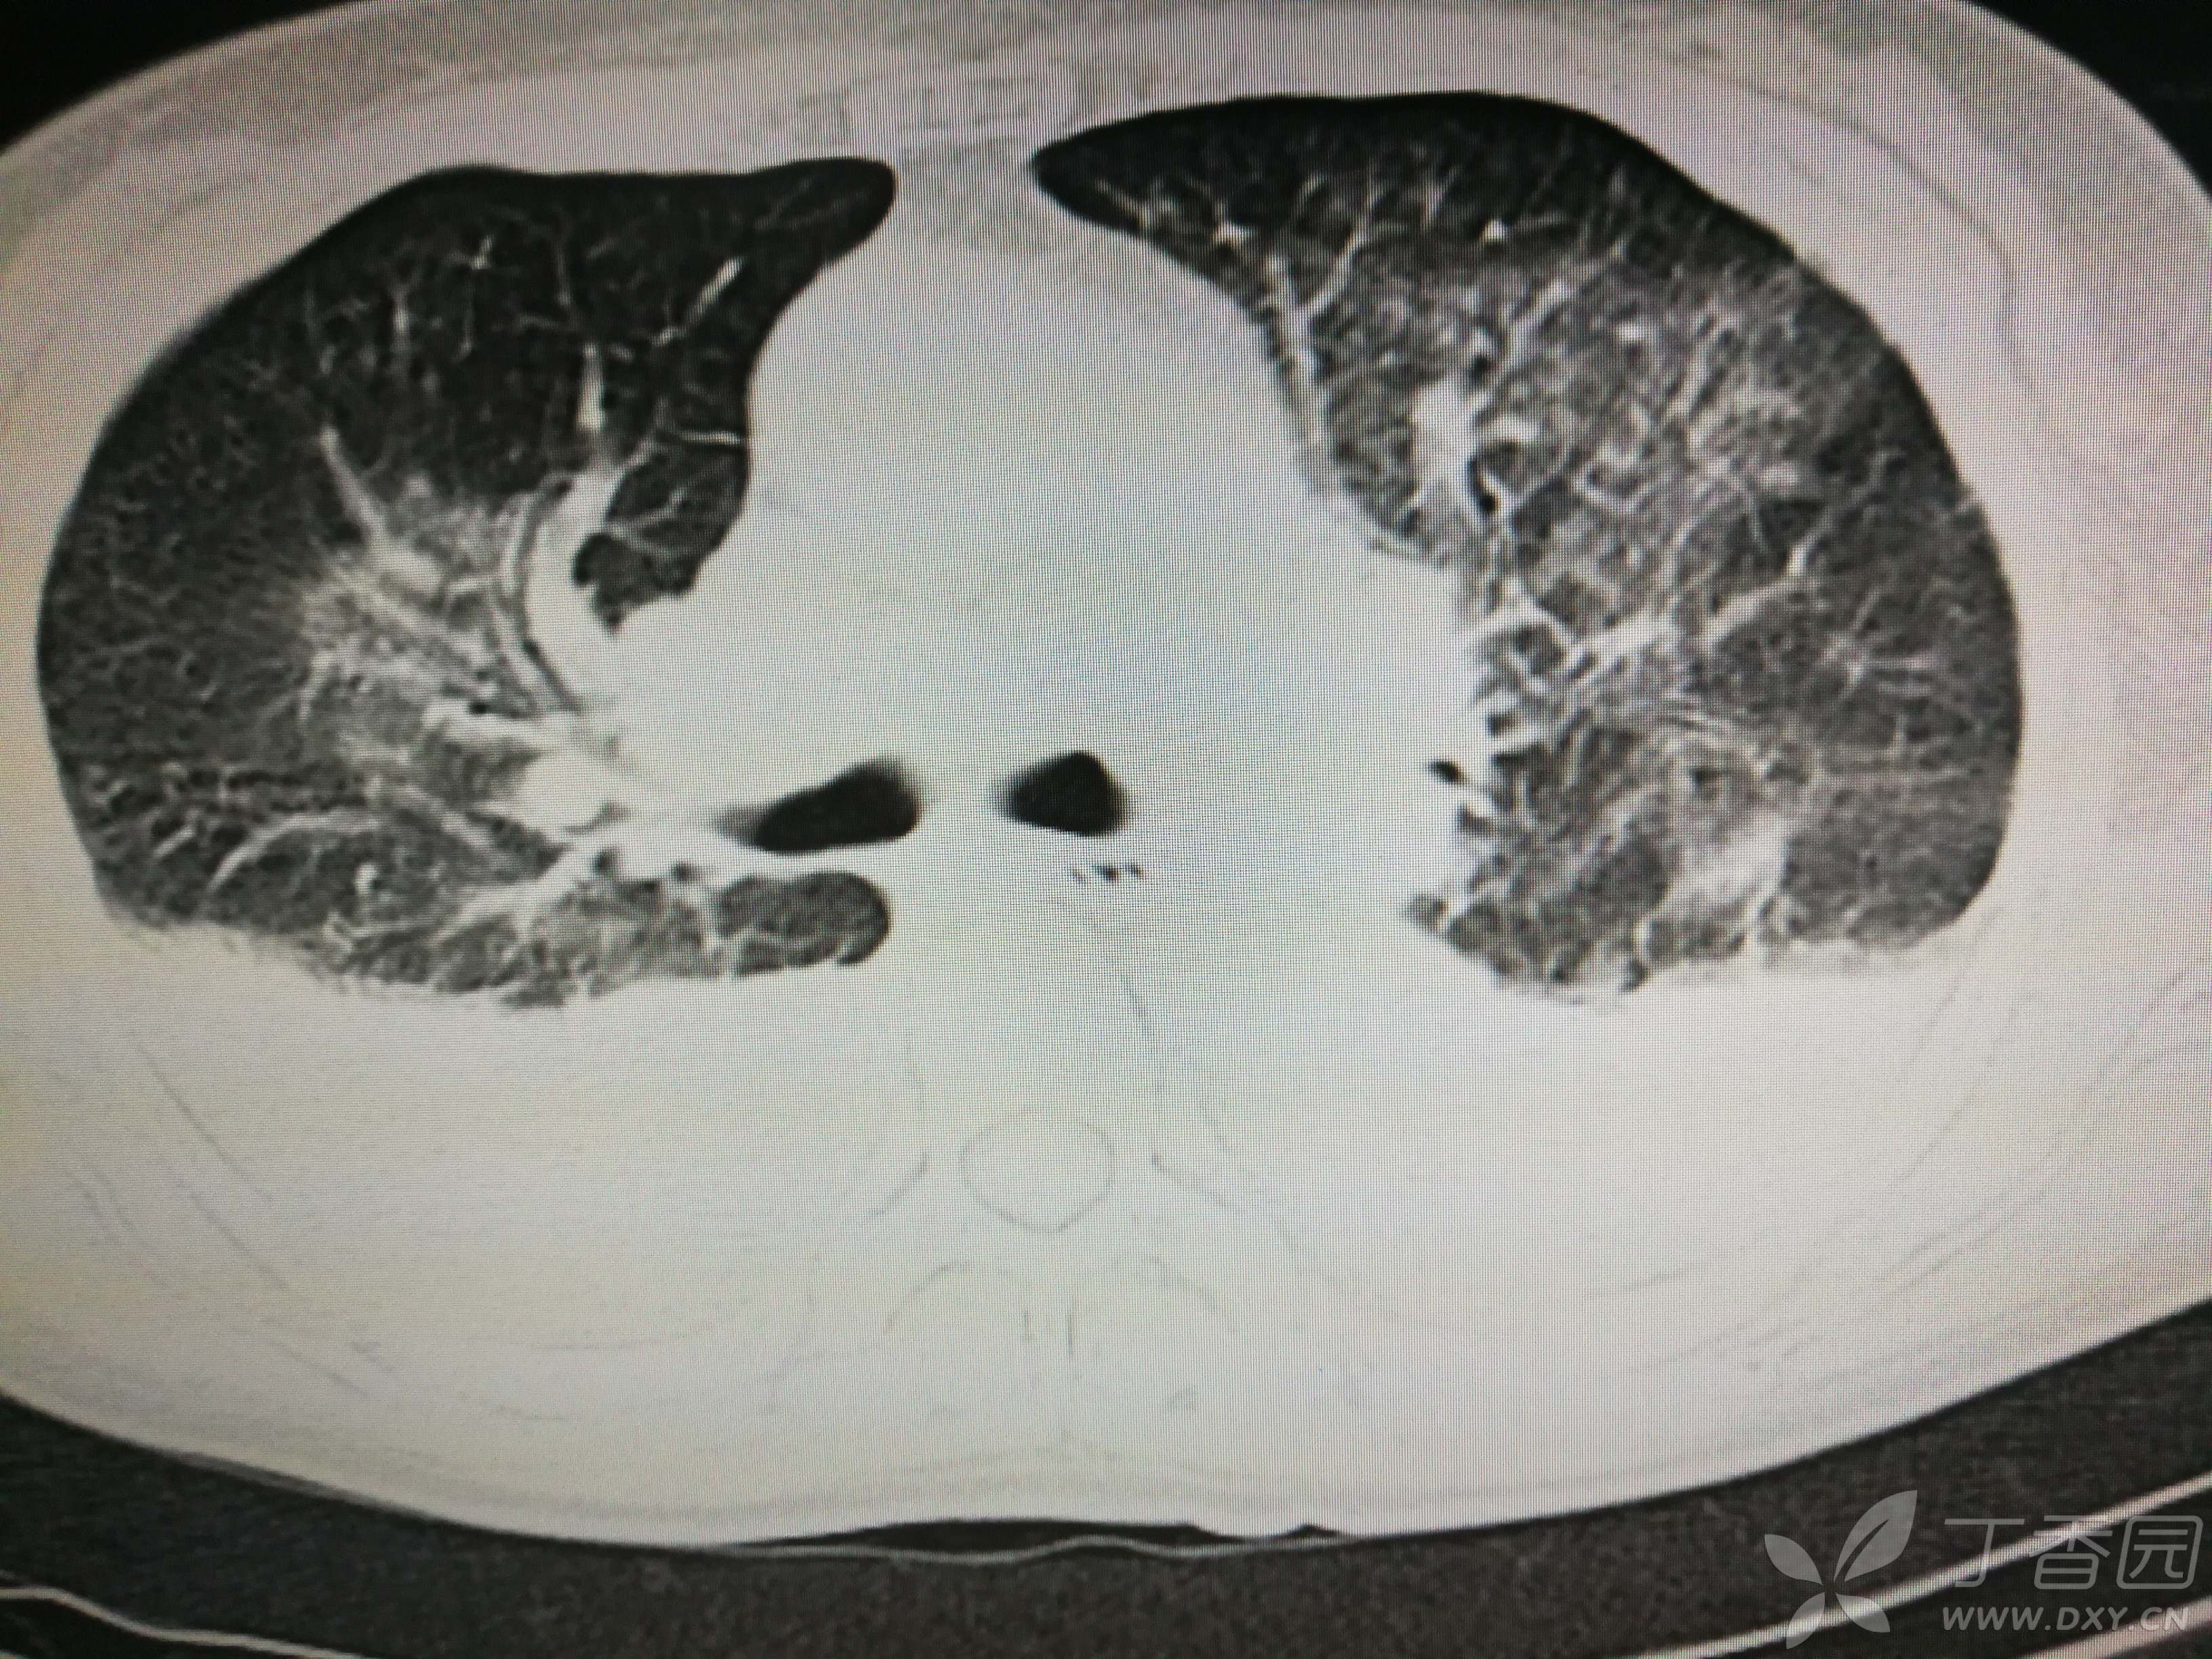

给予低分子肝素钙针抗凝、七叶皂苷钠针消肿及骨牵引固定等等治疗。入院后第四天行“左侧股骨下段骨折切开复位内固定术”(术前查双下肢彩超:双下肢深静脉血流通畅),手术顺利,术后予预防感染、预防血栓形成等治疗。术后患者无明显发热,生命体征平稳。术后第四天复查血常规:白细胞13.4×109/L,血红蛋白84g/L,血小板在正常范围。生化:白蛋白35.7g/L,余无明显异常。当天,患者开始出现轻度胸闷气急,可耐受。术后第五天患者胸闷气急加重,无胸痛,无背痛,无咯血,无意识障碍,无头晕头痛,无恶心呕吐等,急查凝血功能:纤维蛋白原降解产物12mg/L,D二聚体4000ug/L,余无明显异常。查动脉血气分析:pH7.52,氧分压62mmHg,二氧化碳分压30mmHg,碱剩余1.8mmol/L,乳酸1.0mm/L,血红蛋白86g/L。查胸部CT见下(先视频后图片):